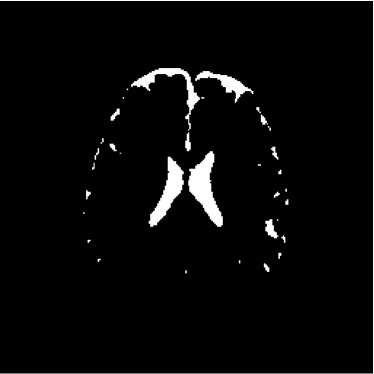

Refer to caption

Figure 14: Ground truth image (13th slice) generated by polynomial net classification

Consequently, the measured similarities between the results obtained by the use of 4-degree and 3-degree polynomial classification related to the 2-degree classification were 0.9816 and 0.9904, respectively. Therefore, we have chosen the result obtained by the 2-degree polynomial classification.

The polynomial net is a 2-layer network, where the first layer is a multiplicative net responsible for the generation of all 2-degree polynomial terms associated to 3 inputs; the second layer is an one-layered perceptron with initial learning rate η0=0.1subscript𝜂00.1\eta_{0}=0.1, training error ϵ=0.05italic-ϵ0.05\epsilon=0.05, and maximum of 200 training iterations. The second layer is responsible for the calculation of the coefficients of the polynomial dedicated to model the discriminant function of each class of interest [39, 41]. Hence, the polynomial net is a polynomial approximator. Learning rate and training error were empirically defined.